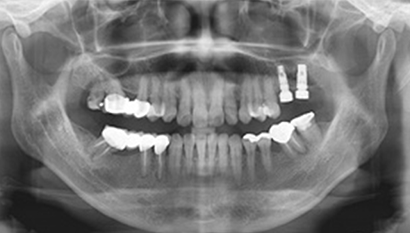

W Dental Clinic Before & After

治療前後の写真

Before

After

上顎洞挙上術です。